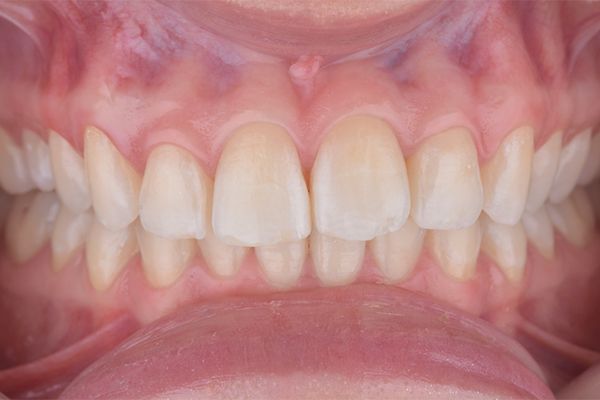

2 | Aspecto inicial, intraoral.

7 | Aspecto final, intraoral.